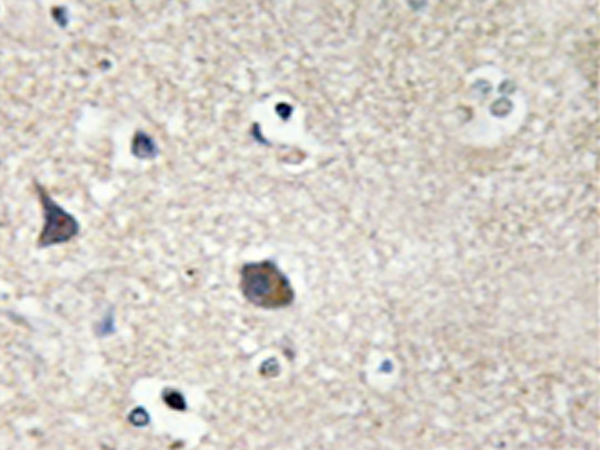

IHC positive control: |

Human brain tissue |

IHC Recommend dilution: |

50-100 |